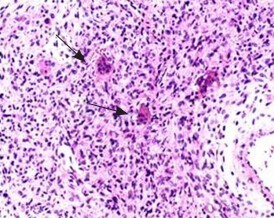

CT诊断:右侧第1肋骨软骨肉瘤可能性大。 治疗:手术治疗。术中牵开前、中斜角肌后可见一约拳头大小病灶,有完整骨性包膜,向下顶压肺尖,向内连于T1椎体横突,包膜部分破裂后有骨样组织溢出。病理诊断为(肋骨)骨巨细胞瘤。

讨论:骨巨细胞瘤好发于长管骨的骨端突出部位,以股骨下端最为多见。肋骨病变侵犯椎体尤为罕见,诊断困难,主要需要和软骨肉瘤、动脉瘤样骨囊肿相鉴别。DOI:10.3969/j.issn.1005-5185.2015.03.016